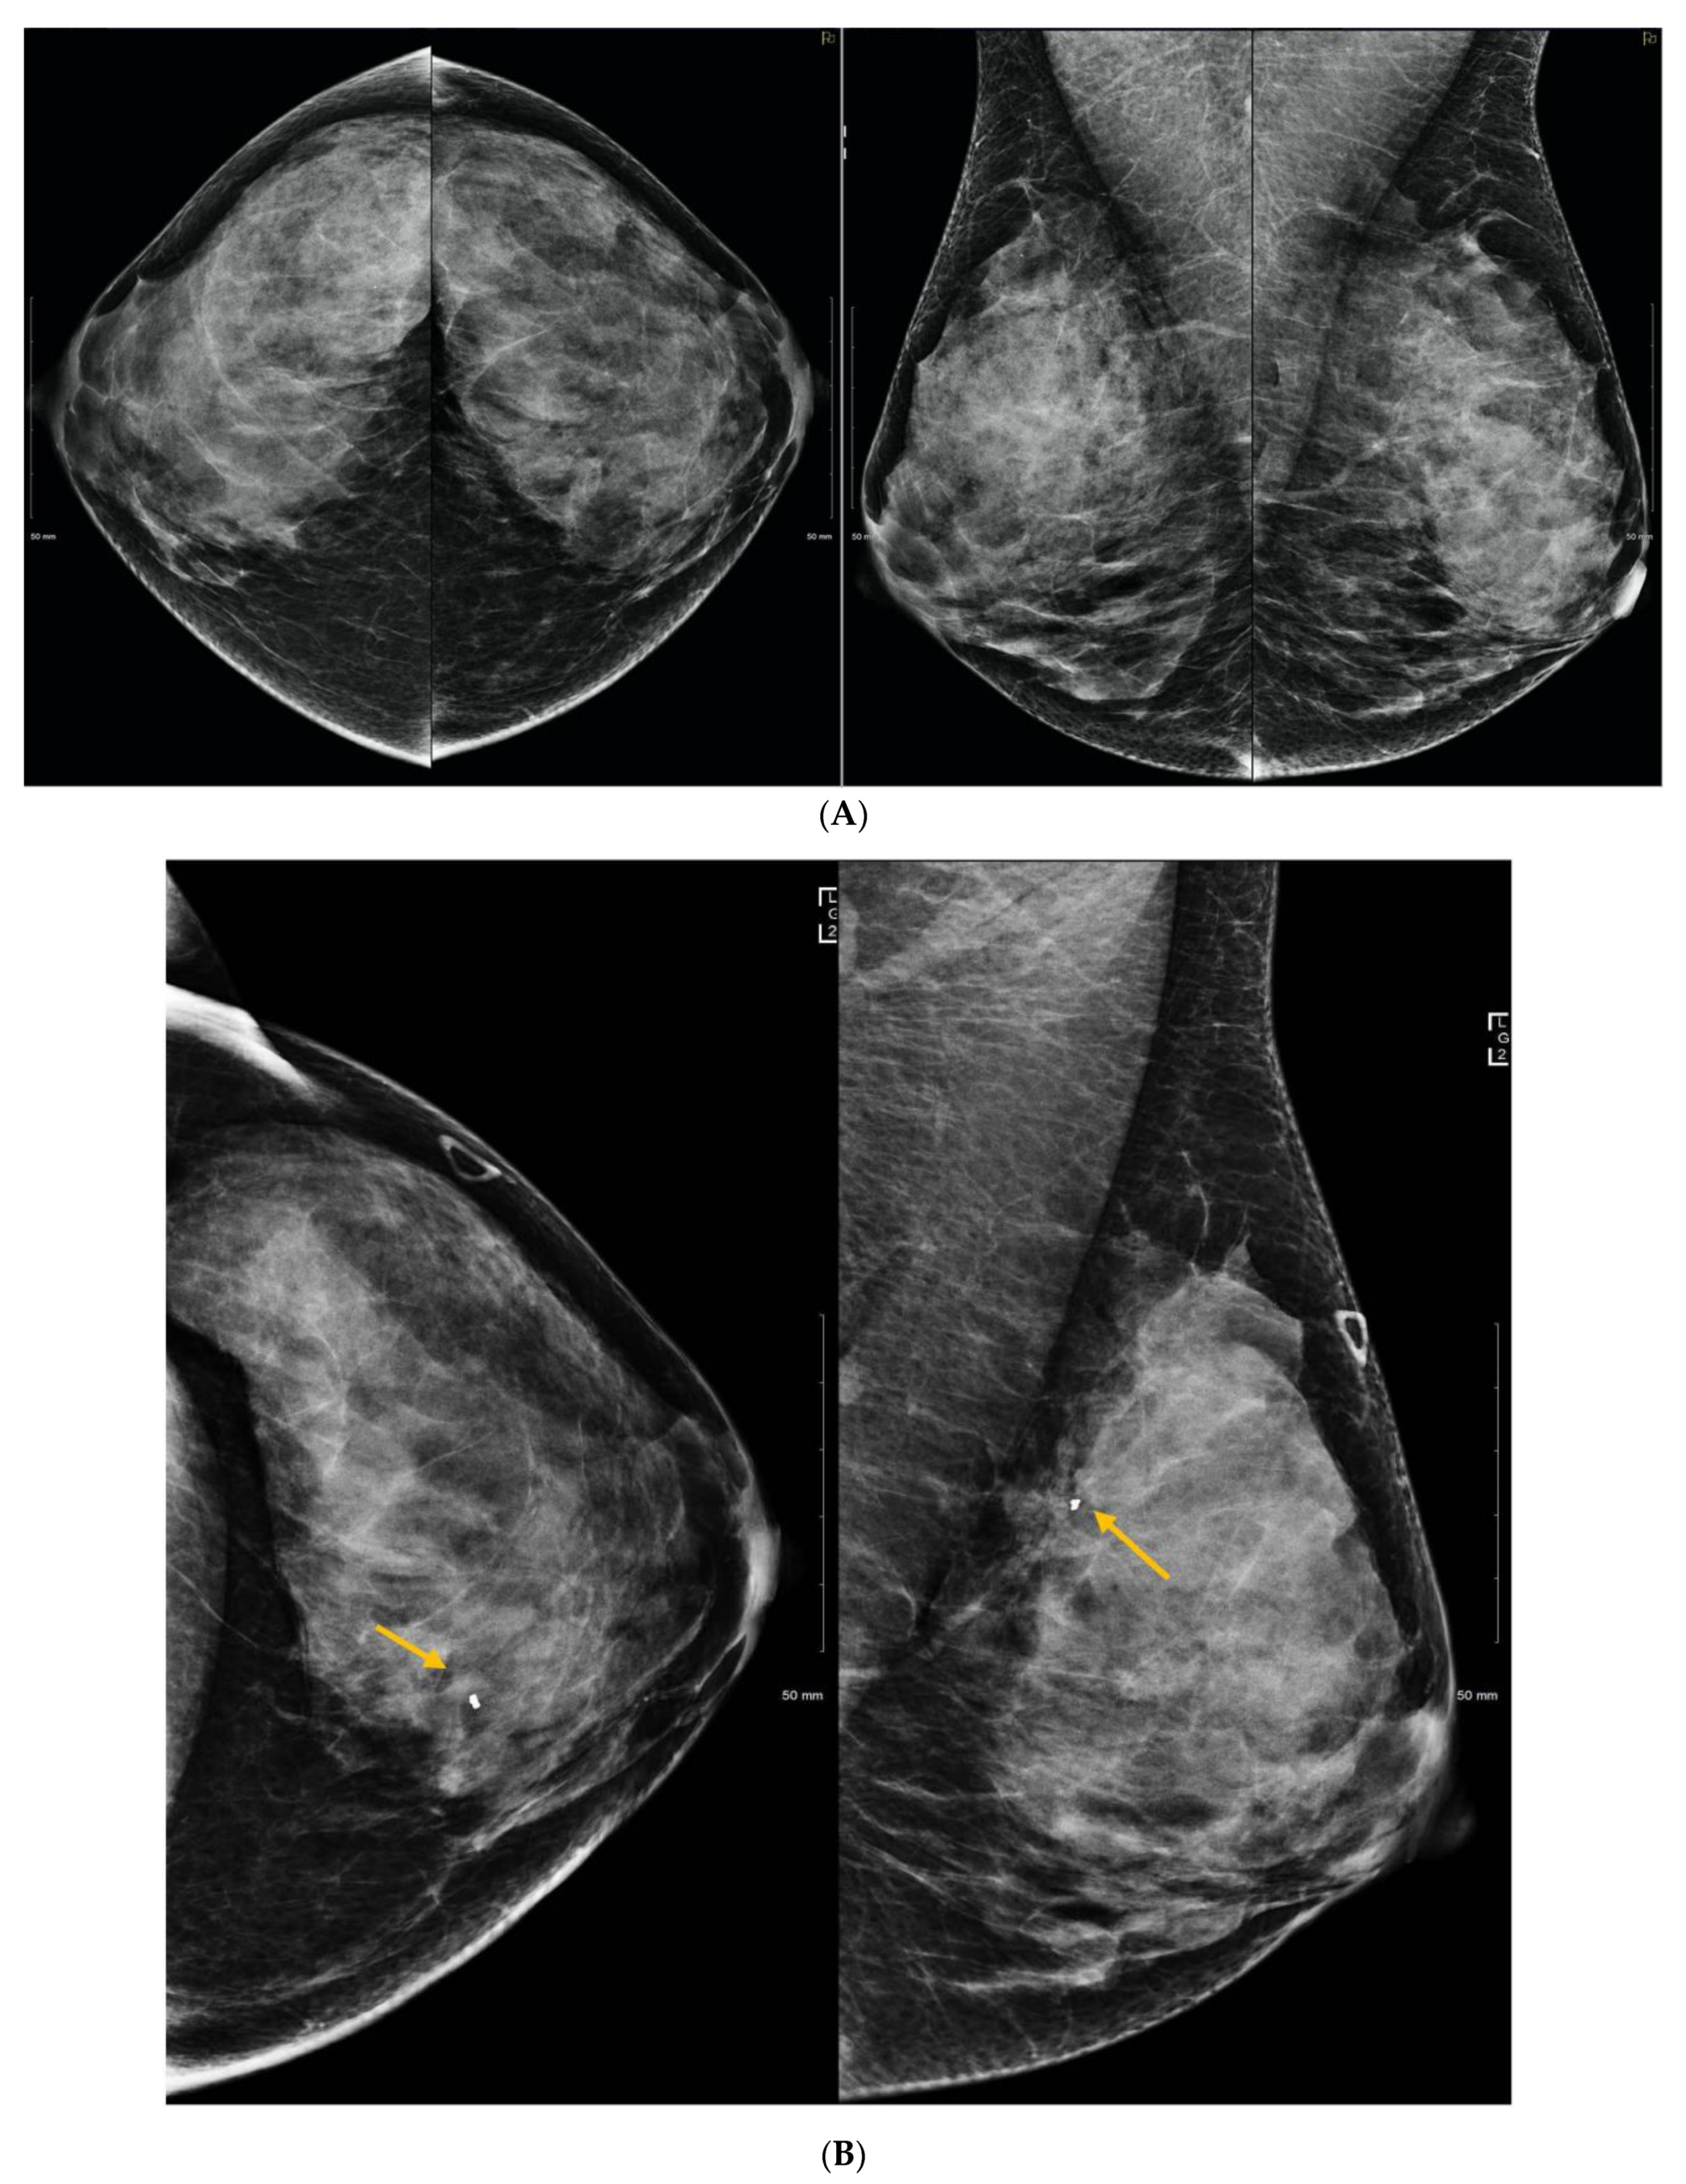

5. Ultrasound (US)